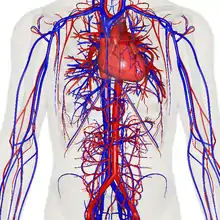

The human circulatory system (simplified). Red indicates oxygenated blood carried in arteries. Blue indicates deoxygenated blood carried in veins. Capillaries join the arteries and veins. | |

The blood circulatory system is a system of organs that includes the heart, blood vessels, and blood which is circulated throughout the entire body of a human or other vertebrate.[1][2] It includes the cardiovascular system, or vascular system, that consists of the heart and blood vessels (from Greek kardia meaning heart, and from Latin vascula meaning vessels). The circulatory system has two divisions, a systemic circulation or circuit, and a pulmonary circulation or circuit.[3] Some sources use the terms cardiovascular system and vascular system interchangeably with the circulatory system.[4]

The circulatory system includes the heart, blood vessels, and blood.[2] The cardiovascular system in all vertebrates, consists of the heart and blood vessels. The circulatory system is further divided into two major circuits – a pulmonary circulation, and a systemic circulation.[8][1][3] The pulmonary circulation is a circuit loop from the right heart taking deoxygenated blood to the lungs where it is oxygenated and returned to the left heart. The systemic circulation is a circuit loop that delivers oxygenated blood from the left heart to the rest of the body, and returns deoxygenated blood back to the right heart via large veins known as the venae cavae. The systemic circulation can also be defined as two parts – a macrocirculation and a microcirculation. An average adult contains five to six quarts (roughly 4.7 to 5.7 liters) of blood, accounting for approximately 7% of their total body weight.[9] Blood consists of plasma, red blood cells, white blood cells, and platelets. The digestive system also works with the circulatory system to provide the nutrients the system needs to keep the heart pumping.[10]

The systemic circulation is a circuit loop that delivers oxygenated blood from the left heart to the rest of the body through the aorta. Deoxygenated blood is returned in the systemic circulation to the right heart via two large veins, the inferior vena cava and superior vena cava, where it is pumped from the right atrium into the pulmonary circulation for oxygenation. The systemic circulation can also be defined as having two parts – a macrocirculation and a microcirculation.[10]

The blood vessels of the circulatory system are the arteries, veins, and capillaries. The large arteries and veins that take blood to, and away from the heart are known as the great vessels.[14]